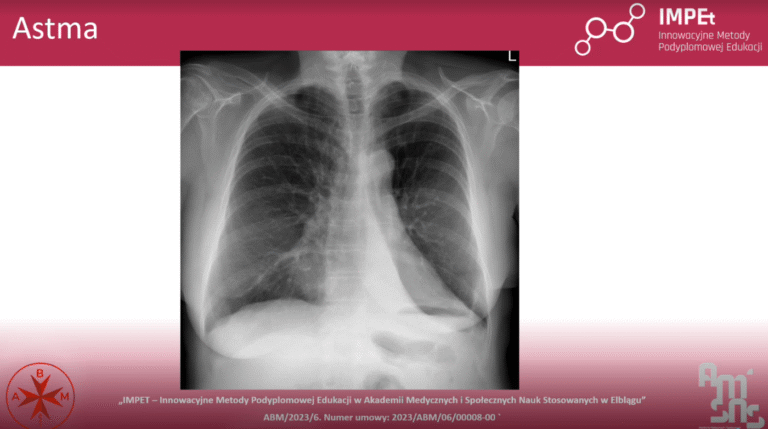

- Diagnostykę chorób, m.in. astmy czy włóknienia płuc,

- RTG klatki piersiowej jako podstawowe badanie obrazowe w pulmonologii.